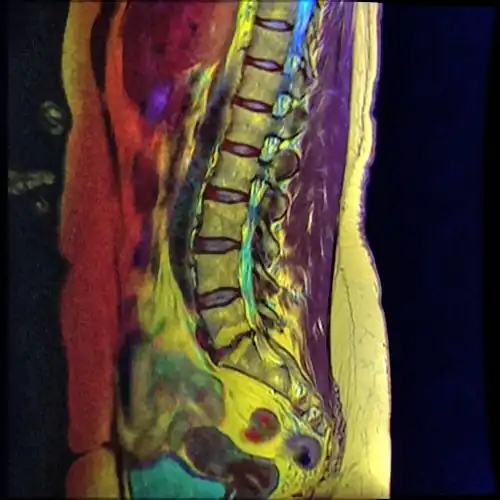

A retrolisthesis is a posterior displacement of one vertebral body with respect to the subjacent vertebra to a degree less than a luxation (dislocation). Retrolistheses are most easily diagnosed on lateral x-ray views of the spine. Views where care has been taken to expose for a true lateral view without any rotation offer the best diagnostic quality.

Retrolistheses are found most prominently in the cervical spine and lumbar region but can also be seen in the thoracic area.